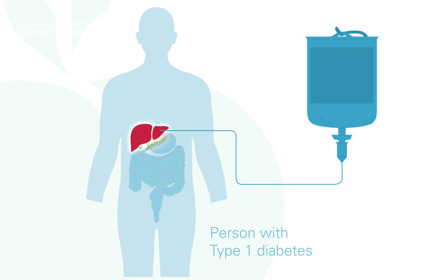

Stem cell-derived islet cells